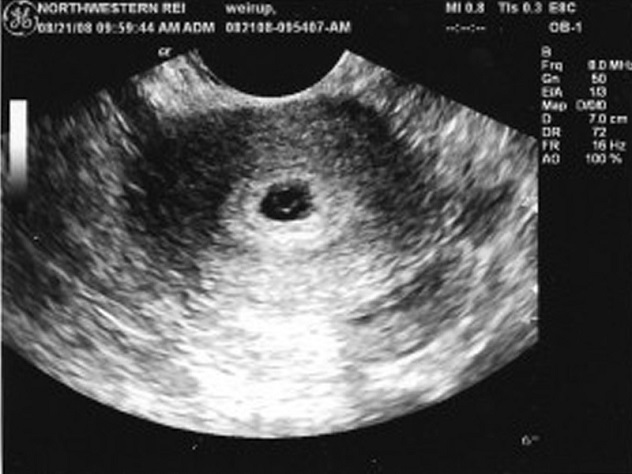

Плодное яйцо в матке — это начальная стадия развития эмбриона, которая формируется после оплодотворения. На ультразвуковом исследовании (УЗИ) плодное яйцо становится видимым примерно на 5-6 неделе беременности. В этот период оно выглядит как небольшое черное образование, окруженное белым контуром, что указывает на наличие жидкости. Эксперты подчеркивают, что раннее обнаружение плодного яйца имеет важное значение для оценки состояния беременности и исключения внематочной беременности. Однако на более ранних сроках, до 5 недель, его визуализация может быть затруднена, и в таких случаях рекомендуется повторное УЗИ через несколько дней для более точной диагностики. Правильная интерпретация результатов УЗИ требует опыта и знаний, поэтому важно доверять квалифицированным специалистам.

Типы УЗИ: Плодное яйцо можно визуализировать как с помощью трансвагинального, так и трансабдоминального УЗИ. Трансвагинальное УЗИ позволяет получить более четкое изображение на ранних сроках беременности, так как датчик находится ближе к матке.

Начнем с ультразвукового исследования, поскольку оно считается наиболее точным и результативным. Проведение процедуры поможет не только диагностировать наступление беременности, но и определить размеры плодного яйца, его форму и местоположение.

УЗИ считается самым точным методом диагностики, особенно если оно проводится трансвагинальным методом, с введением датчика во влагалище женщины.

При проведении такого исследования полученных результатов достаточно для того, чтобы выявить патологию беременности, поставить срок, диагностировать наличие или отсутствие беременности у женщины.